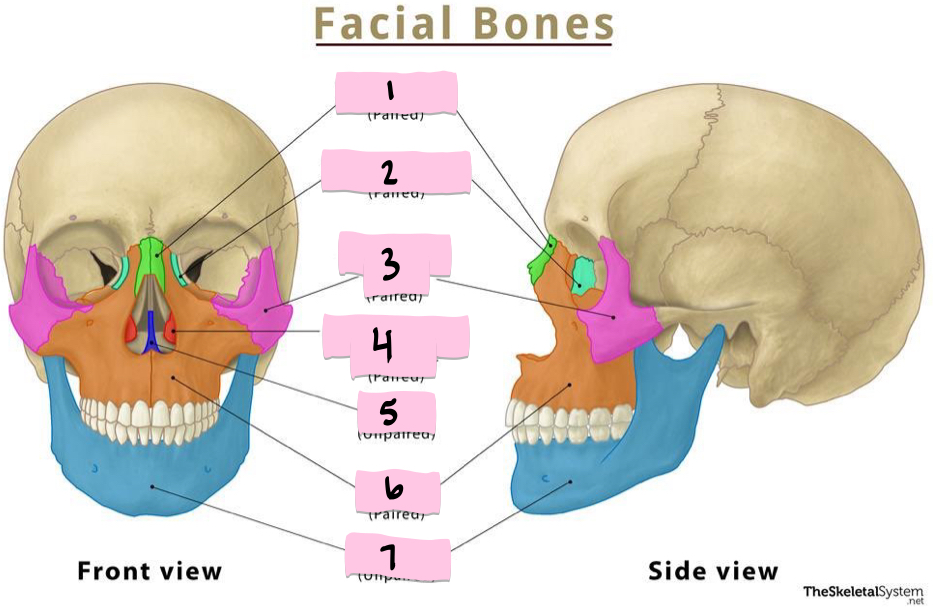

What is 1 pointing to?

Sphenoid bone

What is 2 pointing to?

Nasal bone

What is 3 pointing to?

Lacrimal bone

What is 4 pointing to?

Nasolacrimal canal

What is 5 pointing to?

Ethmoid bone

What is 6 pointing to?

Zygomatic bone

What is 7 pointing to?

Maxilla

What is 8 pointing to?

Mental foramen

What is 9 pointing to?

Mandible

What is 10 pointing to?

Styloid process

What is 11 pointing to?

Mastoid process

What is 1 pointing to?

Nasal bone

What is 2 pointing to?

Lacrimal bone

What is 3 pointing to?

Zygomatic bone

What is 4 pointing to?

Inferior nasal conchae

What is 5 pointing to?

Vomer

What is 6 pointing to?

Maxilla

What is 7 pointing to?

Mandible